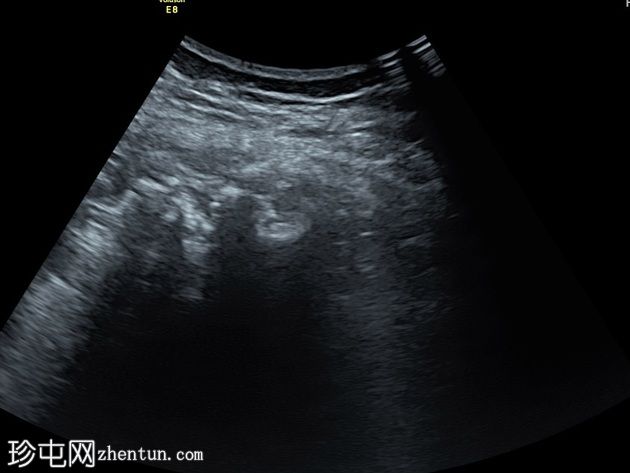

超声

纵切面

患者在局部麻醉下接受了超声引导下经左侧股骨受损皮质的活检。